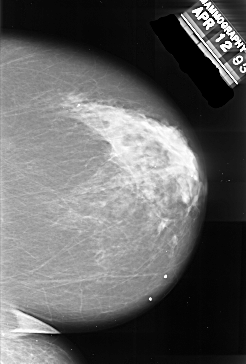

A_1017_1.RIGHT_CC

RIGHT_CC LINES 6541 PIXELS_PER_LINE 4426 BITS_PER_PIXEL 16 RESOLUTION 42 NON_OVERLAY